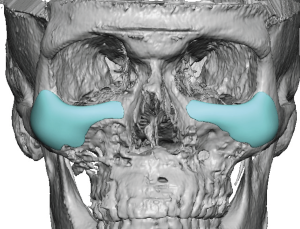

1. Infraorbital Rim Augmentation

- Saddles the infraorbital rim

- Adds both vertical height and horizontal projection

- Produces a superoanterior (3D) expansion of the rim

- Enhances lower eyelid support

2. Medial Extension (Nasal Region)

- Extends toward the nasal bones

- Improves correction of medial tear trough deformity

- Prevents a segmented or disconnected appearance